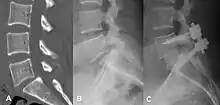

Degenerative spondylolisthesis at L5 - S1.

(A) CT sagittal view of a low grade slip.

(B) Lateral radiograph pre-operative intervention.

(C) Surgically treated with L5 – S1 decompression, instrumented fusion and placement of an interbody graft between L5 and S1.

There are no clear radiological or medical guidelines or indications for surgical interventions in degenerative spondylolisthesis.[46] A minimum of three months of conservative management should be completed prior to considering surgical intervention.[46] Three indications for potential surgical treatment are as follows: persistent or recurrent back pain or neurologic pain with a persistent reduction of quality of life despite a reasonable trial of conservative (non-operative) management, new or worsening bladder or bowel symptoms, or a new or worsening neurological deficit.[47]